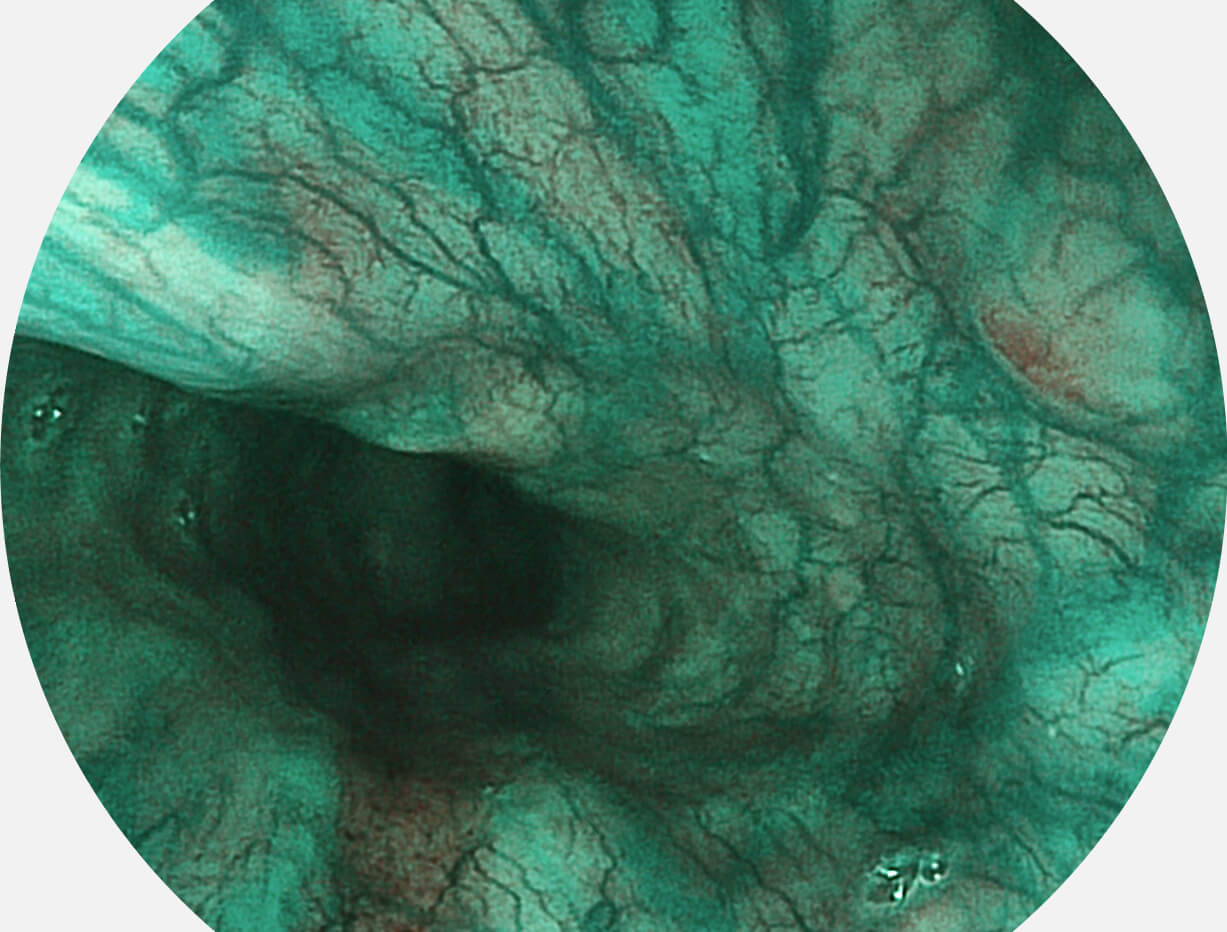

图像具有高亮度、高黏膜血管颜色对比度的特点,且不改变粘液、食物残渣、粪便的基本颜色,可在中远景下进行观察,助力消化道早期疾病的诊断。

SFI图像

白光图像